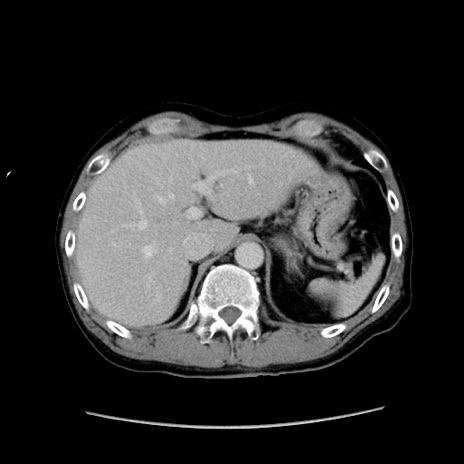

症例37(横断像)

【症例】40歳代 男性

【主訴】腹痛

【現病歴】4時間ほど前に電車に乗車中に臍部上より腹痛出現。徐々に増悪し起立困難となり、救急外来受診。生ものは数日食べていない。今朝お雑煮を食べた。

【身体所見】BT 36.8℃、BP 117/84mmHg、HR 91/min、SpO2 97%、苦悶様、腹部:臍上部広範囲圧痛あり、反跳痛±

【データ】WBC 8100、CRP 0.03